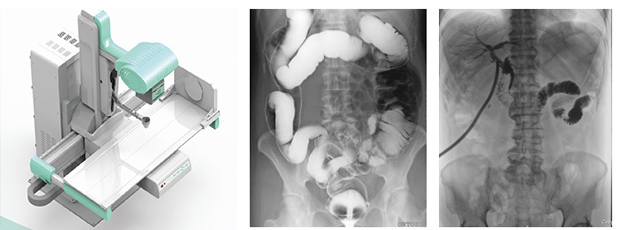

在動態dr成為普放領域大趨勢的當下,越來越多的醫療器械企業宣稱自家擁有動態dr產品。據了解,目前真正掌握核心動態探測器技術的企業寥寥無幾。被蒙蔽的消費者根本區分不清楚真正動態dr是什么樣的,這里,小編就來科普一下真正動態dr必須具備的要素?

1真正動態dr需全面符合我國新監測標準。通過智能算法軟件進行對拍攝時的輻射劑量進行監控并且會在超劑量標準值時進行報警以及采取強制關閉設備措施,全面呵護患者健康。

2、真正動態dr要采用高亮度碘化銫非晶硅動態平板探測器,能實現毫秒級的動靜切換,將動態透視造影與靜態拍片完美結合,這個切換速度保持在0.7秒左右才能滿足臨床要求。

3、真正動態dr是能夠實現高幀率動態視頻拍攝的設備,因此能達到≥30/S,達到日本島津同樣水平的動態dr才是真正有價值的動態dr。這也是與其他偽動態dr較大的區別。

4、真正動態dr需要具有iDGC智能低劑量濾線柵控制功能,與傳統手動人工插拔濾線柵不同的是,本功能能夠根據患者的人群年齡、所需臨床拍攝部位等條件可進行智慧化自動切換合適的濾線柵來獲取高質量圖像,以保證不同患者受到低限度的輻射劑量。

5、真正動態dr需要標配智能脈沖曝光技術,優質的圖像需要高穩定,高頻率的動態高壓發生器與動態平板探測器進行協同,使用傳統的連續曝光輻射劑量大,圖像清晰度也較差,而采用脈沖曝光技術可以降低50%以上患者所受輻射劑量,同時減少運動偽影導致的圖像模糊,提高成像清晰度,輔助醫生進行更加準確的診療。

6、真正動態dr需要具備iACF智能高清點片自動裁切和智能圖像緩存調用系統等圖像算法功能,較大程度提高操作體驗感,支持醫生回放造影視頻,輔助診斷。

動態dr大大提高了普通放射設備準確診斷的能力,為臨床創造了價值。好了,有關真正動態dr就介紹到這了,如果你想了解更多,歡迎關注“普朗醫療器械網”,我們會定期的更新一些新的內容供大家瀏覽閱讀。